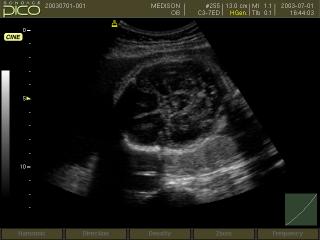

УЗИ аппарат SonoAce-Pico (Medison, снят с производства)

SonoAce Pico - портативный ультразвуковой аппарат компании Medison с цветным допплером и кардиопакетом для исследования сердца плода.

Это современный аппарат для цифрового цветного ультразвукового сканирования. Обладая практически всеми диагностическими возможностями традиционных стационарных сканеров, он является портативным. Благодаря полностью цифровой технологии формирования луча и обработки сигнала, сканер SonoAce Pico позволяет получать изображения с наилучшим для приборов этого класса разрешением. В дополнение к таким технологиям, как формирование трехмерного изображения в ручном режиме и применение широкополосных мультичастотных датчиков, SonoAce Pico имеет функцию формирования трапецеидального изображения, обеспечивающую увеличение поля зрения при исследовании малых органов, возможность использования микроконвексного датчика, а также комплект программ для кардиологических исследований.

Базовая комплектация: сканер SonoAce Pico (монитор 10,4"; встроенные модули: 2-я гармоника, FreeHand 3D, кардиопакет для исследования сердца плода, SonoView Lite; встроенная клавиатура с трекболом), флакон геля 250 мл и руководство оператора.

Акушерские исследования (плод, сердце плода), гинекология (матка, яичники), абдоминальные исследования (печень, желчный пузырь, поджелудочная железа, селезенка, глубокие сосуды), почки.